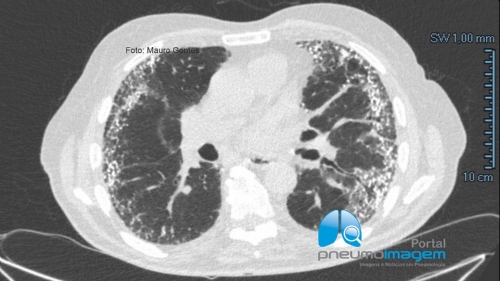

CASO CLÍNICO #58

Homem de 83 anos apresenta-se com cansaço e tosse seca persistente há 2 anos. Perdeu 5kg nos últimos 10 meses. Nega tabagismo. Qual o diagnóstico? Deixe seus comentários abaixo.

83-year-old man presents with tiredness and persistent dry cough for 2 years. Lost 5kg in the last 10 months. She denies smoking. What is the diagnosis? Write your comments below.